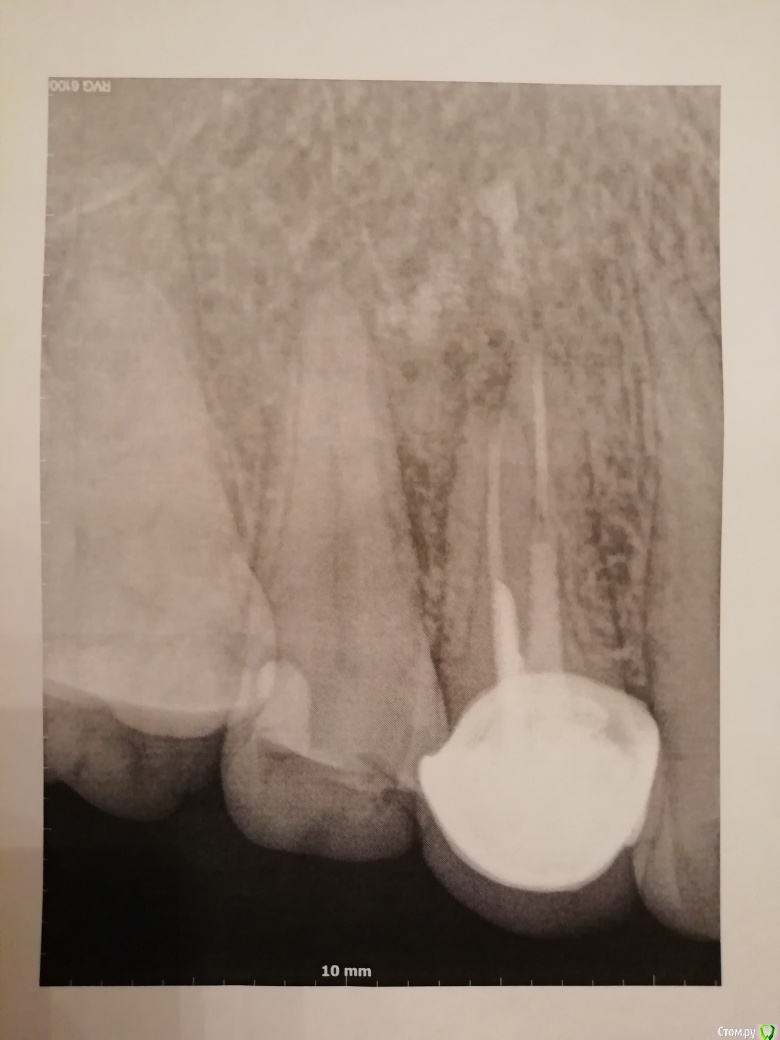

elistac21 Опубликовано 9 января, 2020 Автор Поделиться Опубликовано 9 января, 2020 В продолжение темы. Была сегодня у ортопеда, который мне ставил коронку, по поводу ее снятия для дальнейшего лечения кисты. Сделал еще снимок и сказал, что каналы не перелечить и зуб нужно удалять. Скажите, по снимкам, у зуба нет шансов? Снимки - 3 января в одной клинике, куда обратилась с болью и флюсом, и в другой клинике старый 2010 г (без коронки) и сегодня, 9 января. Ссылка на комментарий